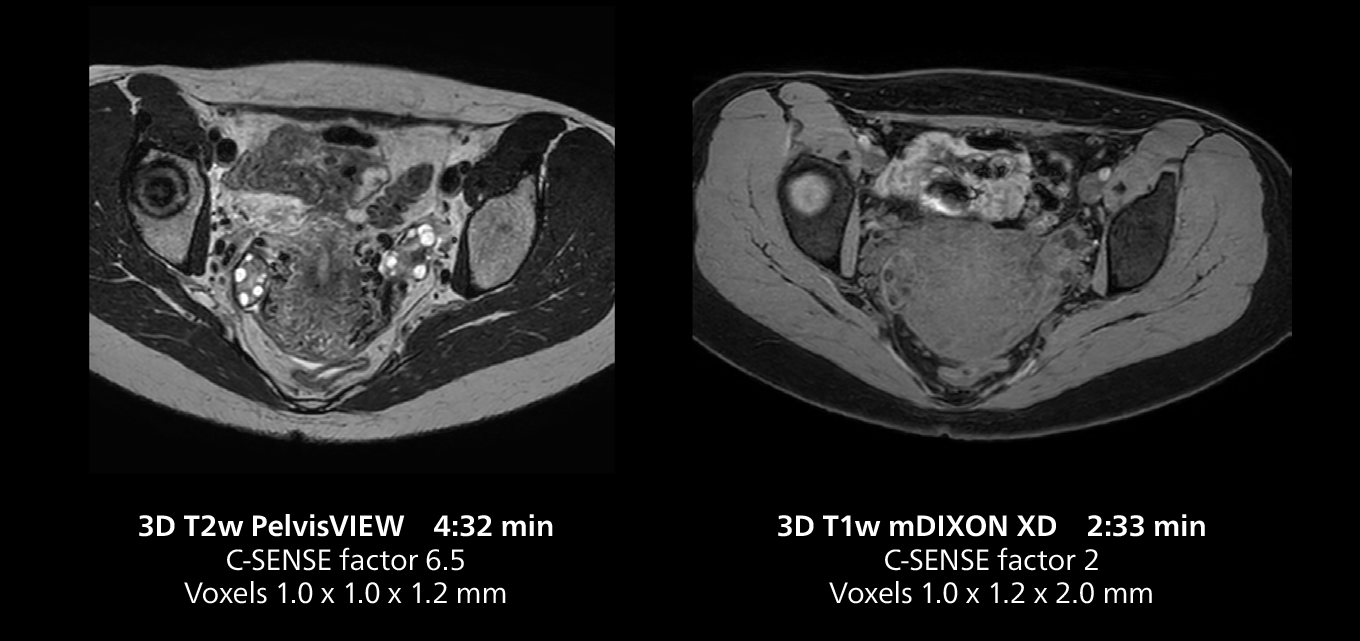

This MRI case illustrates good resolution and imaging quality obtained within reasonable scan times using the MR 5300 1.5T system with the anterior torso cardiac coil that allows use of a large field of view (FOV).

Dr. Gellée highlights the robust free-breathing scans as “the feature that makes the biggest difference in my daily work. The 3D free breathing sequences are very reproducible, and the axial acquisition is very good. For example, in endometriosis, which is one of my focus areas, it provides high contrast and good resolution so that I can see small details. We also use free breathing for liver and pancreas imaging. In multi-phase liver studies, 4D Free Breathing delivers 3-second temporal resolution, making a dynamic scan with more than one arterial phase possible.”